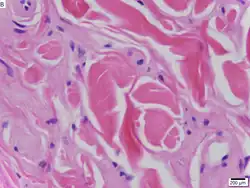

Urbach–Wiethe disease in skin biopsy with H&E stain.

The dermatological symptoms are caused by a buildup of a hyaline material in the dermis and the thickening of the basement membranes in the skin.[9] The nature of this material is unknown, but researchers have suggested that it may be a glycoprotein, a glycolipid, an acid mucopolysaccharide, altered collagen or elastic tissue.[6]